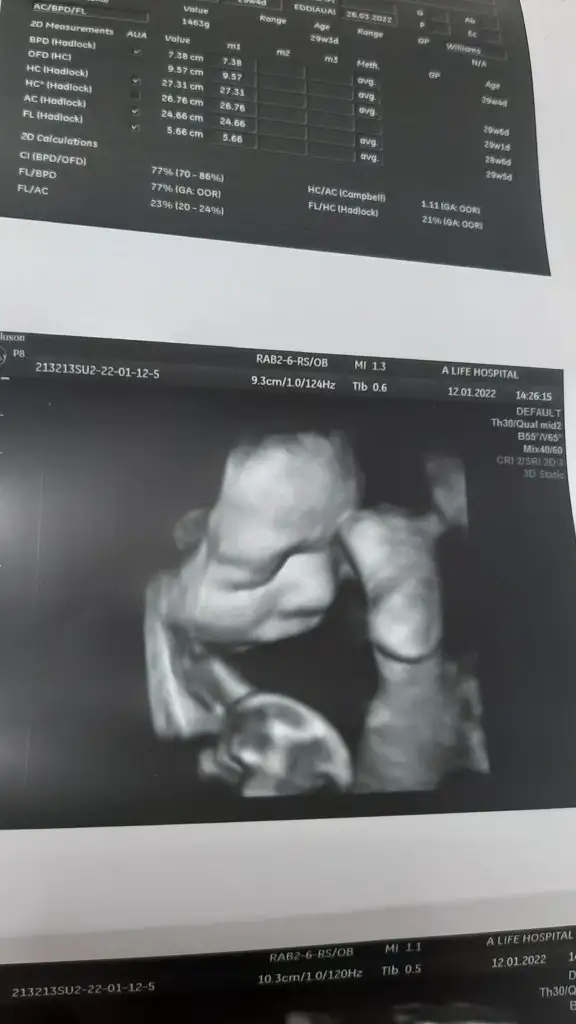

Maşallah canımBende bugün kontrole gittim, iri bir bebek olacak haftasından ileride dedi. Sezeryandan falan bahsetmedi hiç şimdiden, okudumda diyenler olmuş. Bakalım nasip artık